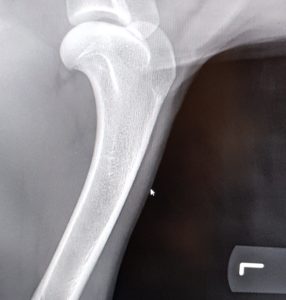

Endnu 2 hunde er blevet bedømt af DKK og fundet HD, AD og OCD frie, vi er så glade og stolte!